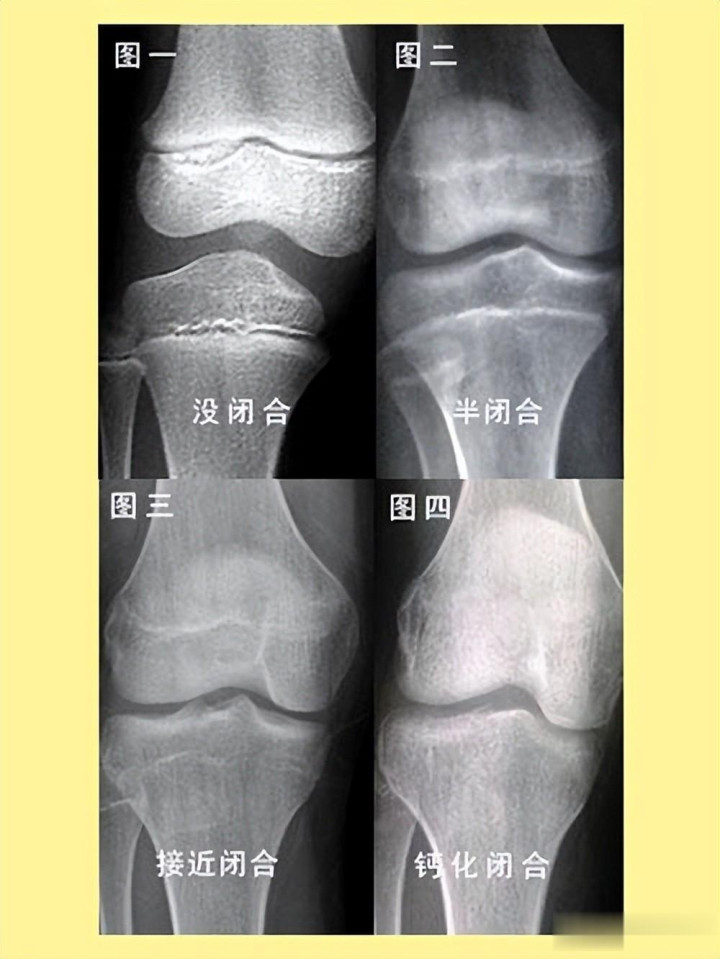

凭证东谈主体剖解学章程,芳华期时骨骺线处于活跃景色,软骨会不断骨化让骨头变长;干与20到26岁,骨骺线会渐渐闭合,软骨皆备钙化成骨,只留住一条淡雅的骺线。